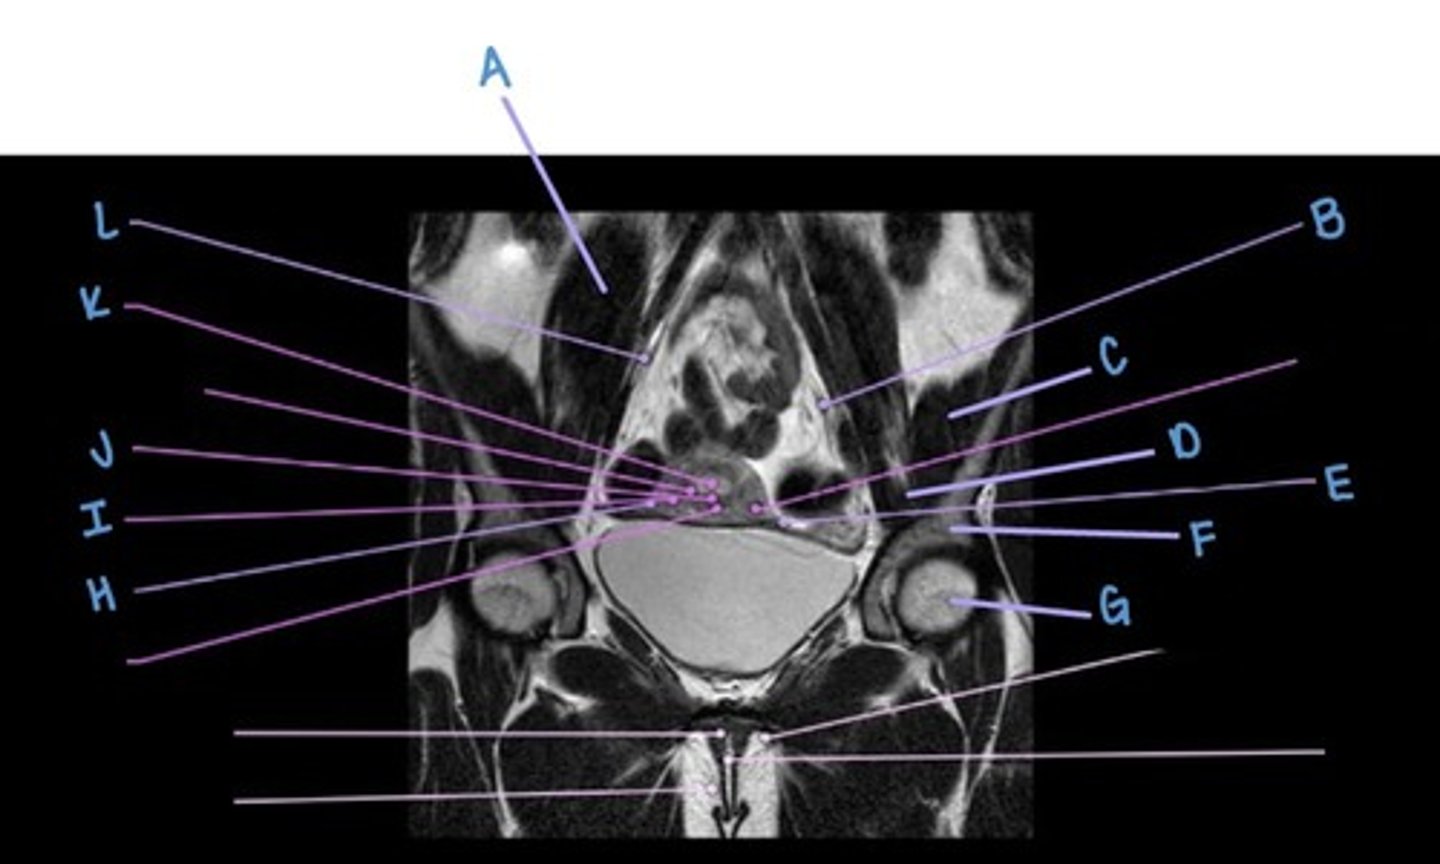

psoas major muscle

A

suspensory ligament of the ovaries

B & L

iliacus muscle

C

iliopsoas muscle

D

uterine (fallopian) tube

E & H

ilium

F

femoral head

G

myometrium

I

uterus

J

endometrium

K